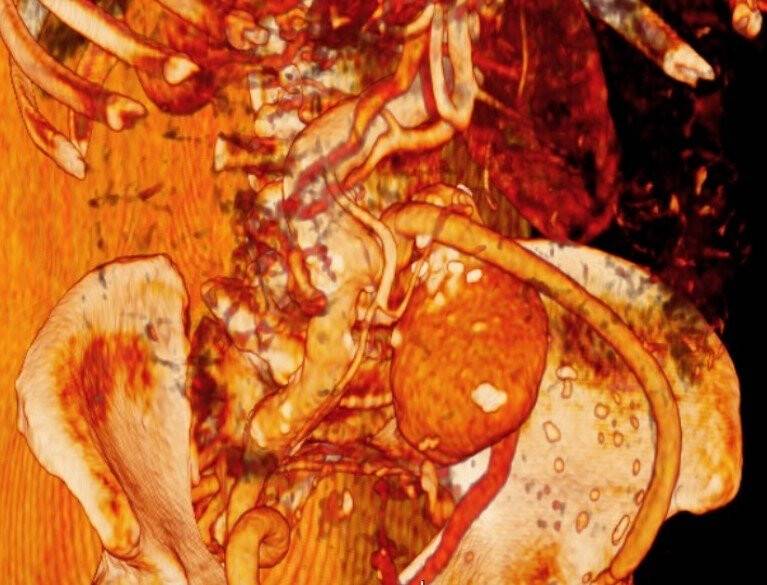

Kahramanmaraş'ın Afşin ilçesinde ikamet eden 85 yaşındaki Fahri Kılınç, yaklaşık 4 yıl süren karın ağrısı ve karnındaki şişlik nedeniyle hastaneye başvurdu. Doktorların tetkikleri sonunda yaşlı adamın karnındaki şişlik incelendiğinde 3 santimetre çapında olması gereken ana aort damarının 15 santimetre çapında büyüdüğü tespit edildi.

Hasta Fahri Kılınç için özel olarak getirilen stent-greft üstü özel bir kumaş kaplı olan tel kafes, hastalıklı damar bölgesine yerleştirildi. Yapılan kapalı operasyon sonrası hastanın damarı normal çapa indirilerek sağlığına kavuştu.

Dr. Mehmet Kirişçi, "Amcamız bize şiddetli bir karın ağrısı ile başvurdu. Daha önceki yapılan tetkiklerde karın damarında balonlaşma söylenmiş ve ileri bir merkeze gitmesi söylenmiş ve balonlaşan damarın tamir olması gerektiği gibi bilgiler söylenmiş bu şikayetler ile bize başvurdu ve hastayı muayene ettik. Kendimiz de filmler çektirdik ve karnındaki ana aort damarın ciddi oranda balonlaştığını gördük. Normalde olması gereken 2-3 santimlik damar çapının 15 santimetre çapına ulaştığı ve damar duvarını da incelenerek her an patlayacak pozisyonda olduğunu gördük. Bu durumu hastamıza ve yakınlarımıza ifade ettik ve tedaviye başladık. Genişleyen damarın tamir kısmı açık ameliyat şeklinde yapılması ölüm riskli bir ameliyattı. Yaptığımız değerlendirmeler sonunda hastayı kapalı yöntemle zorda olsa operasyona aldık" dedi.

Kılınç'ın karnındaki damarın karpuz büyüklüğünde olduğunu söyleyen Dr. Kirişçi, "Normal şartlarda bu çap oluşana kadar ölümle sonuçlanabilirdi. Nihayetinde biz, hastamızın kasığından girerek anjyo-greft ile özel olarak getirttiğimiz stent-greft ile kapattık ve orada balonlaşan damarı tamamen kapattık. İşlem sonrası hastamızın var olan şikayetleri geriledi. Balonlaşan damarın kanlanması da kapandı ve oradaki anevrizmatik yapıyı ortadan kaldırmış olduk. Hastamız gayet konforlu ve taburcu noktasına geldi. Yani damarı balon gibi düşünelim ve büyüdükçe patlama riski artar. Yani damar standardın üzerinden yaklaşık 10 santimetre büyümüş. Eğer buraya gelmeseydi ölümle sonuçlanabilirdi" dedi.